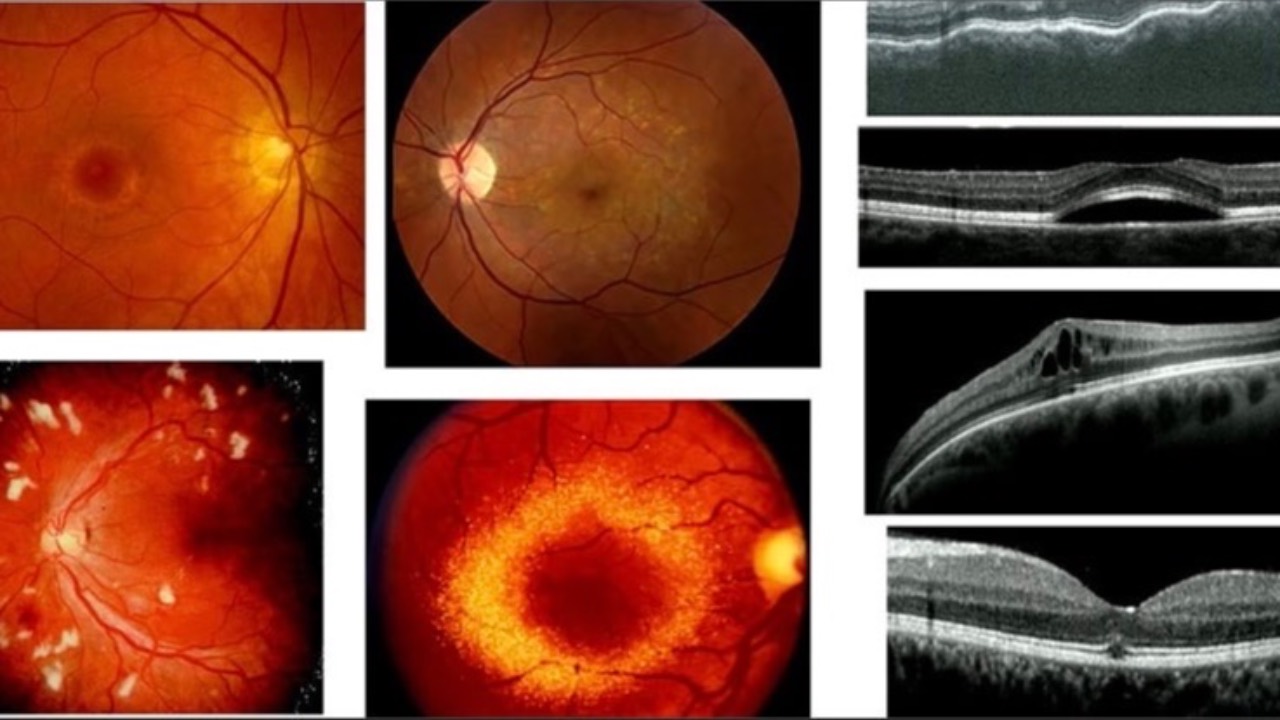

Ocular Toxicity & Systemic Medication

Ocular toxicity due to systemic medication can present a significant challenge in daily practice, requiring appropriate management and interdisciplinary collaboration. We should be reminded to fully understand the pharmacology of each and every medication our patients are...

Purtscher-Like Retinopathy with Systemic Lupus Erythematosus

BMC Ophthalmology recently published a case of a 25-year-old patient who presented with sudden bilateral vision loss, revealing a rare case of simultaneous bilateral Purtscher-like retinopathy associated with systemic lupus erythematosus (SLE).

Exam showed retinal edema, artery narrowing, and s...